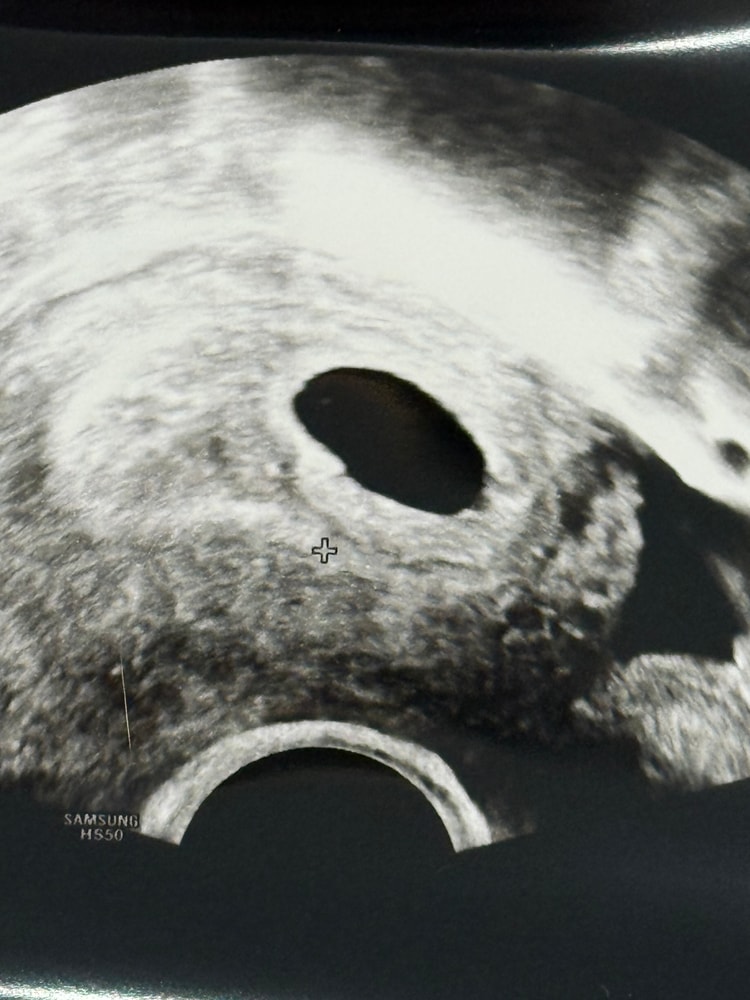

Результаты УЗИДевочки, всем привет! Расскажу немного пред историю. 6 ноября была подсадка эмбриона ( 5 дневка). С 14 дпп сдача хгч , фото динамики ниже. 1 декабря пришла на первое узи, плодное яйцо 7 мм, желточный мешок 2 мм, эмбрион не визуализируется, срок по узи 5 недель. Назначили хгч и повторе узи через неделю. Хгч вырос. Сегодня 8 декабря, пришла на узи , плодное яйцо 11 мм, жм 2 мм, эмбрион не видят. Врач сказала, что подозревает анэбрионию. Вышла и расплакалась от этого. Девочки, на каком сроке у вас был виден эмбрион? И может ли быть такое, что при наличии желточного мешка - нет эмбриона ?

Мне перенесли 8 ноября, на два дня позже вас. Результат узи прикладываю. Срок акушерский был 6и3, но по узи 5и5. Хгч у меня был в динамике

Я думаю может у вас просто поздняя имплантация была, не расстраивайтесь, я б сходила в другое место на узи🫶🏻